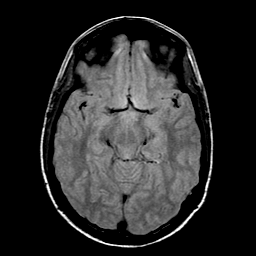

Sarcoma, MR Study #1 mr-pd -- Slice #9

[Home][Help][Clinical] Slice 9